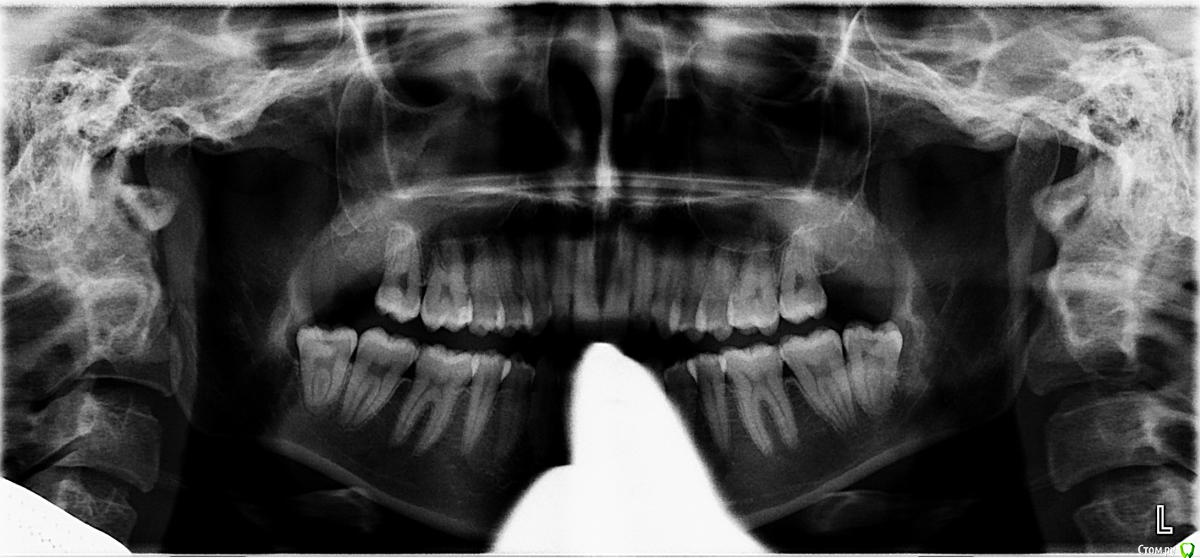

Xerx Опубликовано 20 июля, 2019 Поделиться Опубликовано 20 июля, 2019 (изменено) День добрый.Дёрнули верхнюю восьмёрку. Быстро, легко - минуты 1.5-2.Поднывало, поднялась температура до 37.2 в тот же день. Острой боли не было. Сгусток не выполаскивала, ничего не трогала.Дальше напрягало то, что всё вроде заживало, но температура болталась в районе 37-37.6 полторы недели, было болезненное состояние, как будто болеешь чем-то. Припухла десна - не на самом месте удаления, а между челюстями и внизу.Первый раз пошла провериться к хирургу через 3 дня - "всё норм".На 6 день стало давить висок со стороны удаления. Давило чёрт знает как в течение 2 дней, потом стало поменьше. Опять пошла к хирургу - из-за боли и температуры. На что получила - "это какие-то ваши болезни, с зубом не связано, если бы было связано, вы бы тут от боли на стенку лезли".Сходила к другому хирургу - "Всё у вас хорошо, ничего такого не вижу, лунка заживает. Дёсны припухли, т.к. ваш зуб теперь щёку не держит и вы их закусываете".ОК.Постепенно стало давить не только висок, но и скулу, неприятные ощущения в ухе. Зачесалась лунку - да так, что я даже ночью проснулась. Потом стали "чесаться" зубы, ныть и тянуть (даже те, в которых уверена, что абсолютно здоровы - передние), на верхней челюсти в основном, иногда весь рот чешется, дёсны, иногда жжёт язык. Никаких высыпаний во рту нет.Если постучать по скуле и надавить на челюстной сустав на стороне удаления, получишь приятный бонус в виде давящей боли на пол-лица и дискомфорта в ухе. Хотя она может возникать и спонтанно.Третий хирург пощупал, сказал, что дело может быть в суставе, лунку вскрывать не надо, вы что, идите к ортодонту.Вот так и живём. Хоть температуры нет и лунка не чешется больше. Это какая-то инфекция ползёт? Что делать? Надо лунку вскрывать? Изменено 20 июля, 2019 пользователем Xerx Ссылка на комментарий

red_butler Опубликовано 21 июля, 2019 Поделиться Опубликовано 21 июля, 2019 Сделайте Кт 15*15 с придаточными пазухами носа, нужно исключить верхнечелюстной синусит Ссылка на комментарий

Xerx Опубликовано 21 июля, 2019 Автор Поделиться Опубликовано 21 июля, 2019 (изменено) Сделайте Кт 15*15 с придаточными пазухами носа, нужно исключить верхнечелюстной синуситОк, сделаю. Вы КЛКТ имеете в виду? Лунку надо вскрывать? Это же из неё инфекция идёт? Изменено 21 июля, 2019 пользователем Xerx Ссылка на комментарий

red_butler Опубликовано 21 июля, 2019 Поделиться Опубликовано 21 июля, 2019 Вы КЛКТ имеете в виду? да Лунку надо вскрывать? Это же из неё инфекция идёт? я этого не говорил... Ссылка на комментарий